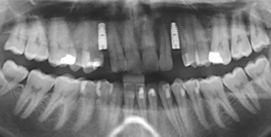

ClinCheck, 3D CT Planung und Röntgenbild

Implantat-Planung im CT mit Implantat

Implantate ersetzen Eckzähne, Röntgenbild